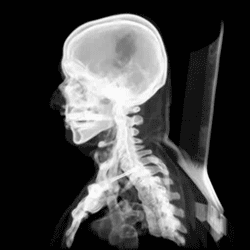

Cráneo

Exploración de la cabeza

• El tamaño del cráneo está determinado por distintos componentes que influyen en su perímetro: encéfalo, líquido céfalo-raquídeo (LCR), sangre y el grosor de los huesos. Su incremento traduce un crecimiento del encéfalo, mientras que su disminución se asocia a una reducción del volumen del parénquima cerebral; de ahí la importancia de su medición, registro y valoración con las tablas de PC en cada control pediátrico

• Se procede a realizar una palpación del cráneo, aplicando una suave presión y movimiento rotatorio desde la frente hacia la parte posterior. Durante este proceso, se busca asegurar que el cráneo se sienta simétrico y uniforme, sin diferenciación de los huesos, ya que generalmente los puntos de fusión no son palpables después de los 6 meses de edad. Sin embargo, en algunos casos se puede percibir el borde de la sutura sagital.

• Además, se examina el cuero cabelludo separando el cabello en busca de quistes u otras lesiones. Es importante que el cuero cabelludo se mueva libremente sobre el cráneo, sin presentar sensibilidad dolorosa, inflamación o depresiones a la palpación. Cualquier hipersensibilidad o presencia de una escotadura, muesca, incisión o depresión en el cráneo puede indicar una posible fractura craneal.

• En cuanto a las deformaciones localizadas, se pueden observar salientes anatómicas anormales como lipomas, quistes dermoides, hematomas o aneurismas cirsoideos, que son malformaciones vasculares que pueden palparse y ser detectadas mediante auscultación.

• En lactantes, se debe prestar atención a la fontanela anterior hasta los 9-18 meses y la fontanela posterior hasta los 2 meses, ya que pueden presentar depresiones normales en estas áreas. Después de estos períodos, la presencia de fracturas de cráneo debe ser considerada en caso de detectar depresiones.